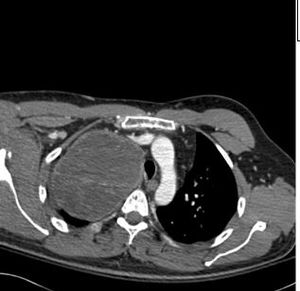

The mediastinal benign schwannomas is a nerve sheath tumor composed of Schwann cells. These tumors are often asymptomatic and found incidentally.